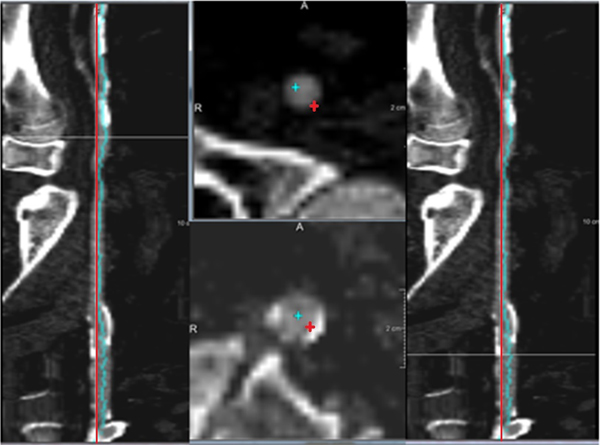

Next, the centerlines in the femoral arteries were improved by a centerline refinement step. For this, a multi-scale medialness response based wave-propagation scheme [14] was used. First, multi planar reconstruction (MPR) transversal image slice stacks were generated according to the initial centerline along the femoral artery. Next, the medialness response was computed from a circle centered at the initial centerline point, with multi-scale radius. This response was constructed as to give high values inside the center of the lumen and lower values inside calcifications. The response was used as the speed function for the wave propagation and back tracking method to generate the final refined centerline. Figure 2 shows an example of the comparison of the automatic extracted centerline and the refined centerline.

Result of centerline refinement step. The red crosses are the original centerline points; the blue crosses are the refined centerline points. The blue points avoid the calcium, and are better located in the middle of the cross-section of the artery lumen compared to the red points